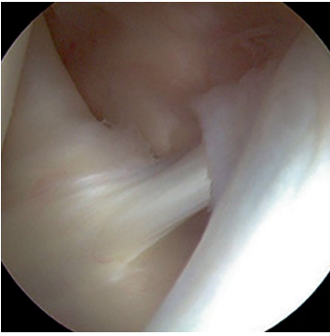

Die Bezeichnung adhäsive Kapsulitis, die 1945 vom amerikanischen Chirurg Dr. Neviaser gewählt wurde, ist nach den heutigen Erkenntnissen der Erkrankung ziemlich irreführend. Frozen Shoulder betrifft in erster Linie die Schultergelenkkapsel, welche sich durch Entzündungsprozesse verdickt und dadurch die Beweglichkeit einschränkt. Sie ist nicht verklebt oder angewachsen.

Normale Schulter Entzündete Kapsel bei Frozen Shoulder